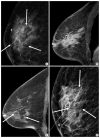

Imaging features of breast cancer molecular subtypes: state of the art

Characterization of breast cancer molecular subtypes has been the standard of care for breast cancer management. We aimed to provide a review of imaging features of breast cancer molecular subtypes for the field of precision medicine. We also provide an update on the recent progress in precision medicine for breast cancer, implications for imaging, and recent observations in longitudinal functional imaging with radiomics.